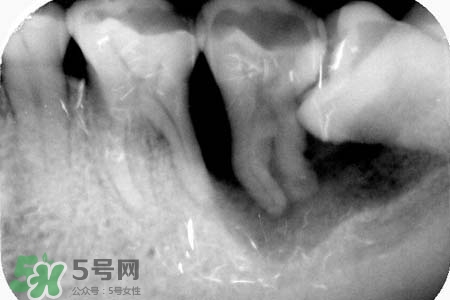

長(zhǎng)智齒一般不會(huì)引起耳鳴,智齒冠周炎時(shí)可能會(huì)引起耳部放射性疼痛。耳鳴因素很多,若持續(xù)時(shí)間較長(zhǎng),因及時(shí)就醫(yī)。如果確定耳朵沒(méi)有問(wèn)題,那么智齒導(dǎo)致的,癥狀是非常可能的智齒阻生,應(yīng)盡早拔除,萌出空間不足、反復(fù)引起發(fā)炎也可考慮拔除。